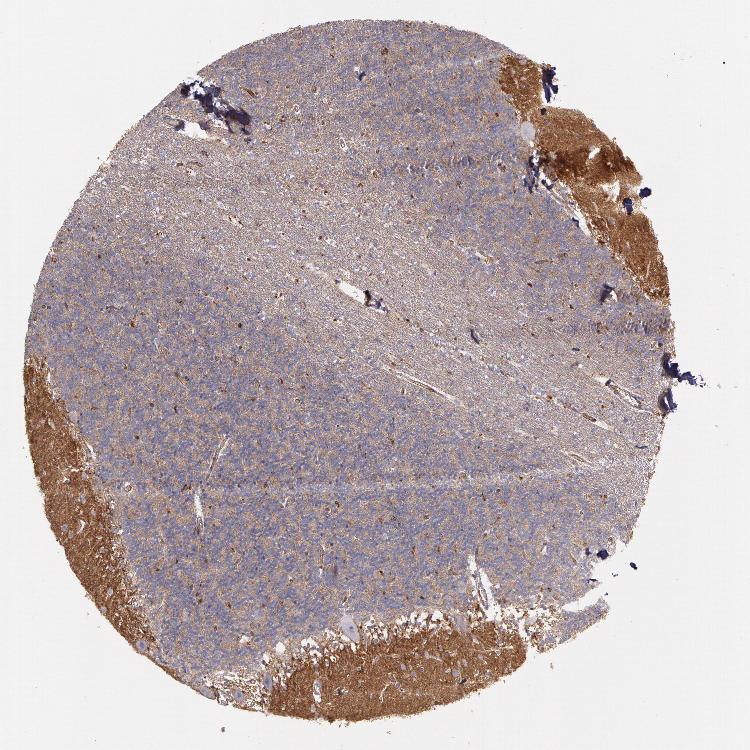

BRAIN CEREBELLUM Show tissue menu

CEREBELLUM - Expression summary

CEREBELLUM - Antibody stainingi

Antibody staining in the annotated cell types in the current human tissue is reported as not detected, low, medium, or high, based on conventional immunohistochemistry profiling in selected tissues. This score is based on the combination of the staining intensity and fraction of stained cells.

Each image is clickable and will lead to virtual microscopy that enables deeper exploration of all samples and also displays staining intensity scores, fraction scores and subcellular localization as well as patient and tissue information for each sample.

Antibody HPA001396Antibody CAB004395

Purkinje cells Not detectedLow

Cells in granular layer LowMedium

Cells in molecular layer LowHigh